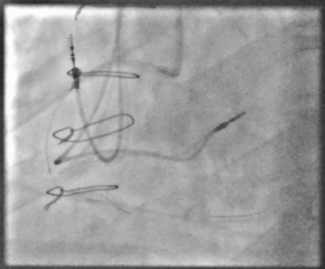

When dislodged stents remain on the coronary wire, the wire can be snared outside of the body. These two cases demonstrate the use of the presnaring technique to retrieve dislodged coronary stents when the stent remained on the coronary wire.